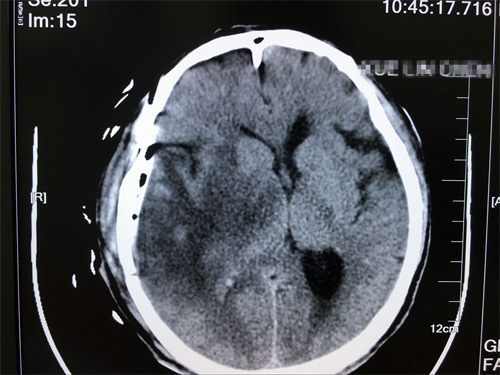

術(shù)后影像:未見腫瘤殘余,未見異常明顯病灶

手術(shù)后第3天,陳老漢平安轉(zhuǎn)到普通病房,術(shù)后第5天,引流管順利拔除,在家人的照顧下,恢復(fù)越來越好。薛老漢的女兒說:“真的非常感謝沈教授,以很快的速度幫我們解除了痛苦,現(xiàn)在父親終于不要再受腦瘤折磨了?粗眢w一點點好轉(zhuǎn),我們做子女的遺憾也少一點”。除了感謝沈教授,薛老漢的女兒還對醫(yī)院的服務(wù)贊不絕口,她說:“父親在這里住院,一個病房的患者和家屬相處都非常融洽,醫(yī)生每天查房,很有耐心,護士姑娘們也非常溫柔,脾氣很好。馬上就要出院了,真的十分感謝各位病友和醫(yī)護人員的照顧”。

在手術(shù)過程中,沈建康教授在顯微鏡下利用工具非常嫻熟地進行探測、剝離、止血、沖洗,不放過任何一個可能隱藏腫瘤的部位,用鑷子和剪刀將腫瘤物夾取,剪取... 最后,護士將器皿中的腫瘤物放入標(biāo)本瓶,送去進行病理化驗。手術(shù)后,薛老漢被送到重癥監(jiān)護室密切觀察。他意識清醒,表達無誤,四肢活動無障礙。其實在膠質(zhì)瘤切除手術(shù)過程中,有兩個難點,一個是腫瘤邊界判斷,盡可能保證全切,另一個是神經(jīng)功能保留,讓患者在術(shù)后有較高的生活質(zhì)量,這兩點,沈教授都做到了。